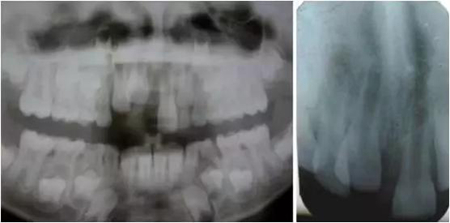

影像學(xué)檢查:根尖片以及全景片(圖2)提示牙槽骨骨折,根尖挫入至唇側(cè)骨板或鼻底。根尖片提示牙11,12 和21根尖發(fā)育不完全,呈喇叭口狀。受累牙的根管壁薄且不完全成形(圖2)。牙片顯示沒有冠折和根折。

診斷:牙11嚴(yán)重挫入,牙12中度挫入,牙21震蕩傷。

( 圖2)